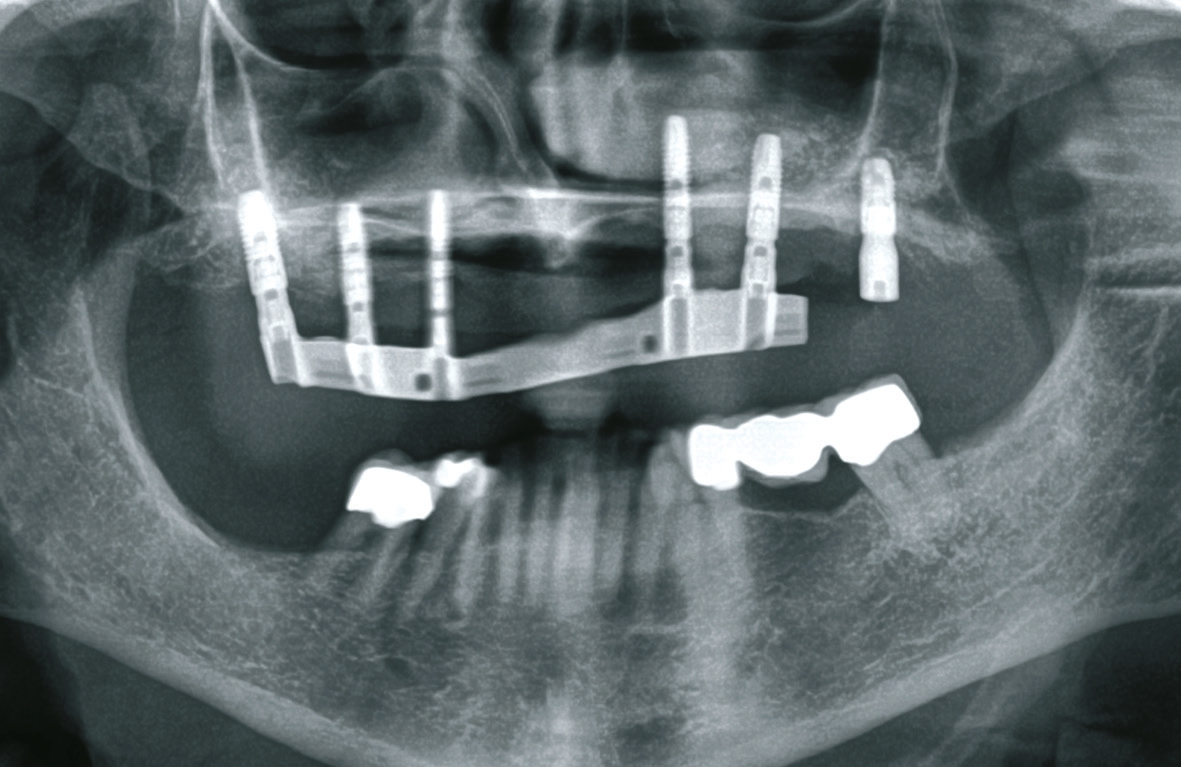

Vor dem zweiten OP-Eingriff nach 4 Monaten wurde im Labor eine Bohrschablone hergestellt. Zudem wurde ein DVT angefertigt, um im Sinne eines backward planning die idealen Implantatpositionen zu ermitteln. Bei Eröffnung des augmentierten Kieferbereiches zeigte sich eine gute Regeneration und Revaskularisierung des Knochens. Sechs Implantate konnten mit ausreichender Länge und passendem Durchmesser so in den augmentierten Bereich (Astratech EV®, Dentsply Sirona Implants, Mannheim) inseriert werden, dass sich eine gleichmäßige Pfeilerverteilung ergab (Abb. 7 u. 8).

Bei der Eingliederung des Steges wurde festgestellt, dass das Implantat regio 27 nicht osseointegriert war. Möglicherweise war dies auf eine ungenügende Regeneration des in dieser Region verwendeten Knochenersatzmaterials im Rahmen des Sinuslifts zurückzuführen. Das nicht osseointegrierte Implantat wurde folglich entfernt, ebenso das nicht umgewandelte Knochenersatzmaterial (Abb. 17). Daraufhin wurden mit der Luerzange autologe Knochenpartikel aus dem Tuber entnommen und in Region 27 appliziert. Der Zahntechniker kürzte die Stegarbeit ein (Abb. 18), die nun nur auf den 5 gut osseointegrierten Implantaten ruhte. Während der kompletten Ausheilungsphase im Bereich des entfernten Implantates regio 27 konnte die Patientin die angepasste Stegarbeit weitertragen. Nach 3 Monaten erfolgte der Re-entry in dieser Region. Der Situs zeigte sich gut verheilt (Abb. 19a u. b), der Knochen war gut regeneriert und die Nachimplantation regio 27 wurde vorgenommen (Abb. 20). Nach weiteren 4 Monaten Einheilphase erfolgte die Freilegung des neuen Implantats regio 27. Dieses zeigte sich diesmal gut regeneriert und konnte nun wie geplant der Stegarbeit als sechster Pfeiler dienen.

Die besondere zahntechnische Herausforderung bestand nun darin, das Implantat über ein Abutment in die vorhandene Stegversorgung einzubeziehen. Die genaue Position wurde über eine Abformung mit Laboranalogen bestimmt, kontrolliert durch ein OPG (Abb. 21). Wieder wurde in situ mit einem Übertragungsschlüssel aus Pattern gearbeitet, um das neu zu fertigende Stegstück spannungsfrei anschließen zu können. Nach ausgiebigen Prüfungen wurde die Ergänzung gegossen und nach der Patientenanprobe an den bestehenden Stegbogen angelasert (Abb. 22a u. b, Abb. 23). Es folgte die Herstellung der endgültigen Sekundär- und Tertiärstruktur (Abb. 24). Bei dem hier vorgestellten Patientenfall wurde das Sekundärgerüst herkömmlich gegossen (Brealloy, Bredent, Senden). Lichthärtender Kunststoff sowie Konfektionszähne komplettierten die Arbeit, wobei die Ästhetikanprobe unverändert übernommen wurde.